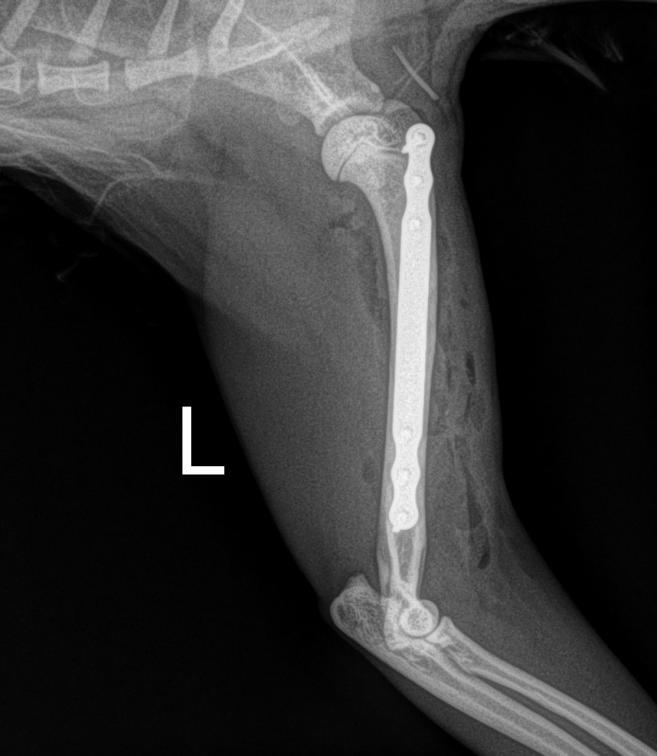

Day 1: He had to fix a humerus spiral fracture (left) with a LeiLOX bridge plate. Furthermore, he diagnosed a femur transverse fracture. Dr. Sonntag then used a 7-hole LeiLOX plate to repair this fracture, and do several emergency soft tissue surgeries.

(Surgery time: 1:15 hours)